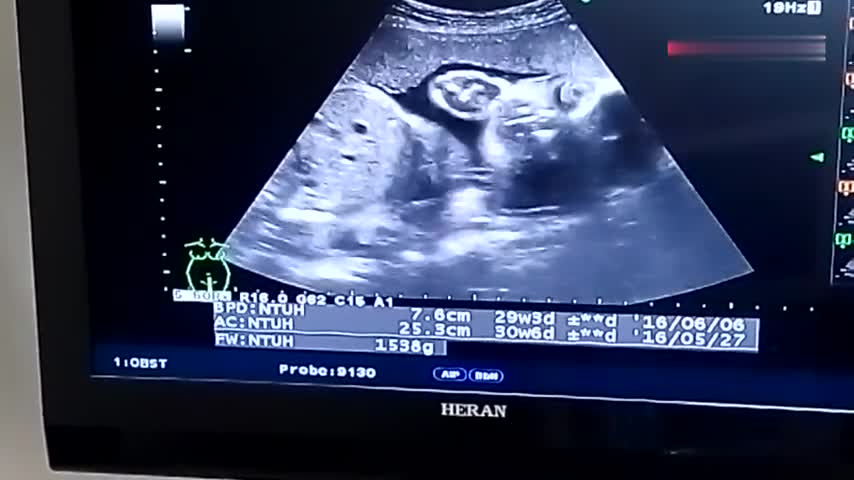

B超单各指标解读方法如下1HC头围头围是评估胎儿头部发育的关键指标,反映胎儿脑部及颅骨的生长情况数值需结合孕周综合判断,若明显偏离参考范围,可能提示发育异常,需进一步检查2BDP胎头双顶径指胎儿头部左右两侧最宽处的直径,通常与HC联合分析孕5个月后,BDP数值应与孕周大致匹配。

一B超单基本信息 1 孕妇信息 姓名年龄孕周如“孕12周+3天”检查日期核对孕周是否与末次月经计算一致,早期B超如孕1114周可通过胎儿头臀长CRL校正预产期2 检查类型 早期妊娠B超确认孕囊胎心胎芽NT检查孕1114周,测颈项透明层厚度大排畸系统超声。

B超单上的专业术语主要涉及孕周判断胎儿结构发育指标胎盘及羊水情况脐血流和胎儿位置等方面,以下为详细解读LMP末次月经时间指孕前最后一次月经第一天的日期,医生会结合该日期与B超检查结果来判断孕周GS胎囊孕早期可见,怀孕6周时胎囊直径约为2cm,孕10周时约为5cm胎囊位置在。